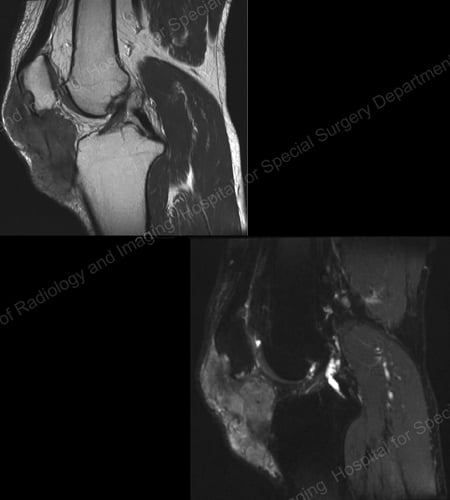

X-rays are the standard imaging technique for gout (See Figures 12-17: Figure 12: Gout of the Base of the 1st Toe; Figure 13: Gout of the Distal Finger Joints; Figure 14: Gouty Change and Soft Tissue Calcification About the Base of the 1st Toe; Figure 15: Gouty Destruction at Multiple Finger Joints; Figure 16: Gouty Erosion at the Proximal Ulna at the Elbow; Figure 17: Large Tophus Seen as Soft Tissue Mass at the Elbow) but in special cases, such as when gout needs to be separated from infection or tumor, magnetic resonance imaging (MRI) (Figure 18: MRI of the Knee Showing Gouty Soft Tissue Mass and Erosion of the Kneecap) or ultrasound (Figure 19: Power Doppler Study Showing Gouty Inflammation at the Base of the 1st Toe) will be helpful. A newer technique called a dual-energy CT scan (DECT) can show urate crystals in green color.

MRI of the knee showing gouty soft tissue mass and erosion of the kneecap

Figure 18: MRI of the Knee Showing Gouty Soft Tissue Mass Erosion of the Kneecap